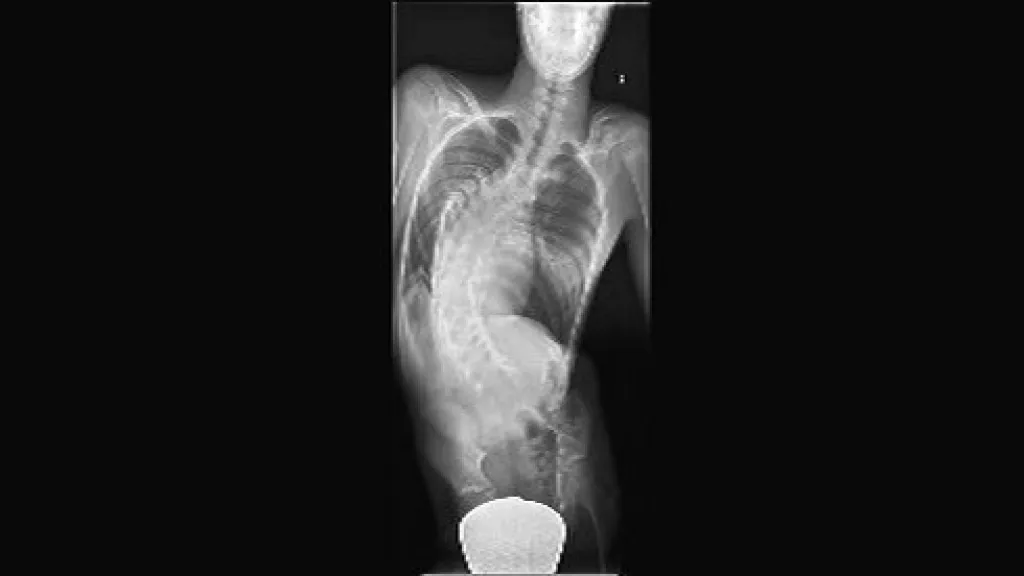

Konstatntin má enormně deformovanou páteř do strany a dopředu, navíc mu chybí i některé obratle a má rozštěpenou míchu. „Základním rizikem u těchto pacientů je, že mohou při operaci ochrnout,“ řekl ČT primář Ortopedické kliniky FN Brno Bohunice Martin Repko.

Lékaři byli na sále šest hodin. Při operaci se snažili rozvolnit páteř a narovnat ji. Obratle pak přišroubovali ke dvěma titanovým tyčím a páteř obložili kostními štěpy. „Po určité době, řekněme po půl roce, se páteř zpevní tím, že sroste v lepším postavení,“ uvedl Repko. Zda byla operace úspěšná, se ukáže během čtrnácti dní. „Bude to v pohodě. Nakonec to zvládneme a problém vyřešíme. Budu hrát zase basketbal,“ doufá Konstantin.